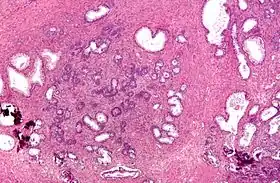

Micrograph showing nodular hyperplasia (left off center) of the prostate from a transurethral resection of the prostate (TURP). H&E stain.

Microscopic examination of different types of prostate tissues (stained with immunohistochemical techniques): A. Normal (non-neoplastic) prostatic tissue (NNT). B. Benign prostatic hyperplasia. C. High-grade prostatic intraepithelial neoplasia. D. Prostatic adenocarcinoma (PCA).